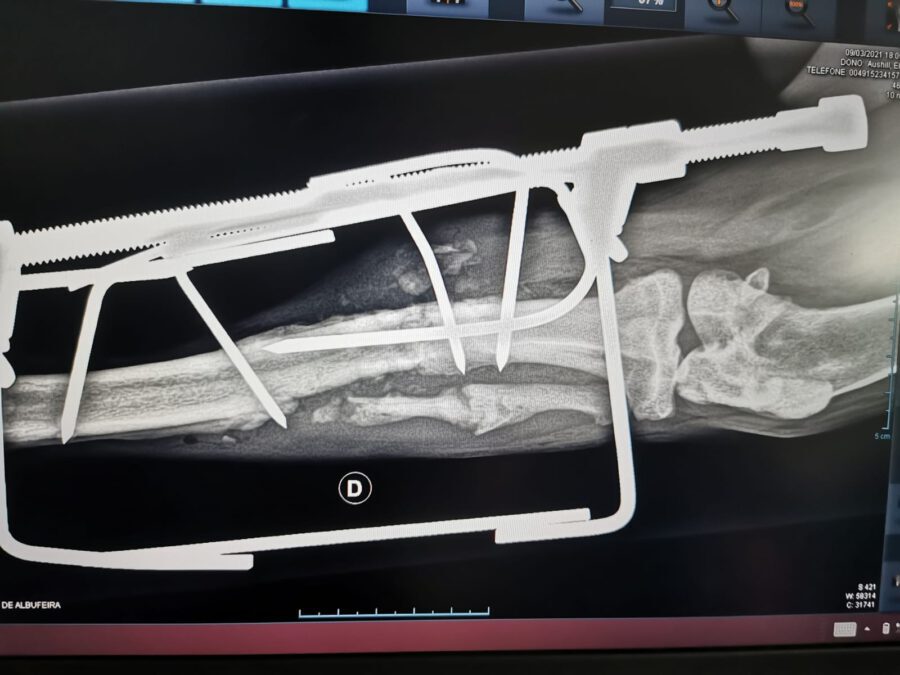

Und erneut erhielten wir den Hilferuf einer engagierten Tierschützerin, die einen verletzten Junghund gefunden hatte, und uns um Hilfe bat. Der kleine Rüde stammt aus einem Zigeunerlager und hatte sich dort das Bein gebrochen. Da sich niemand darum kümmerte, war er gezwungen, mit dem gebrochenen Bein unter Schmerzen herum zu humpeln. Unsere Helfer fuhren sofort los um den armen Schatz einzusammeln und zum Tierarzt zu bringen. Durch ein Röntgenbild ließ sich feststellen, dass das Bein definitiv gebrochen war und unverzüglich operiert werden musste. Glücklicherweise ergaben seine Bluttests, dass er weder an Herzwürmern, an Zeckenbissfieber, noch an Leishmaniose litt.